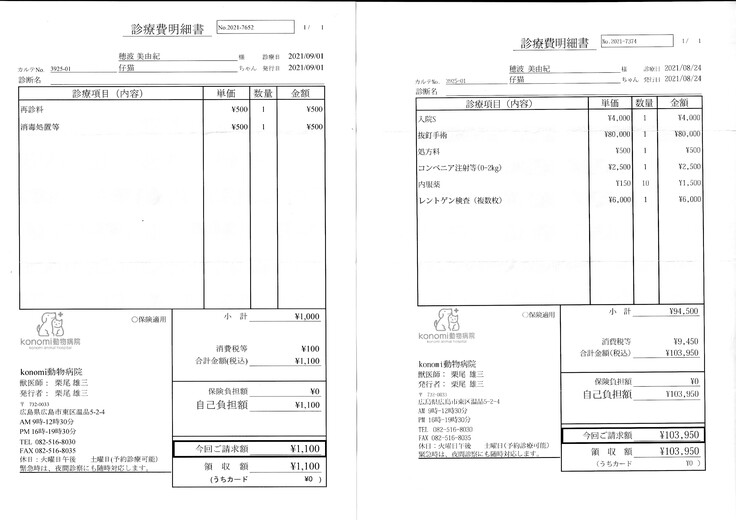

明細書

①入院費用

②退院後の飼育と治療

治療は続いていますが、これまでにかかった費用の一部を皆さまに助けて頂きたく、宜しくお願い致します。

8月24日にスクリューが皮膚から出ていた為、プレートの除く手術を行いました。